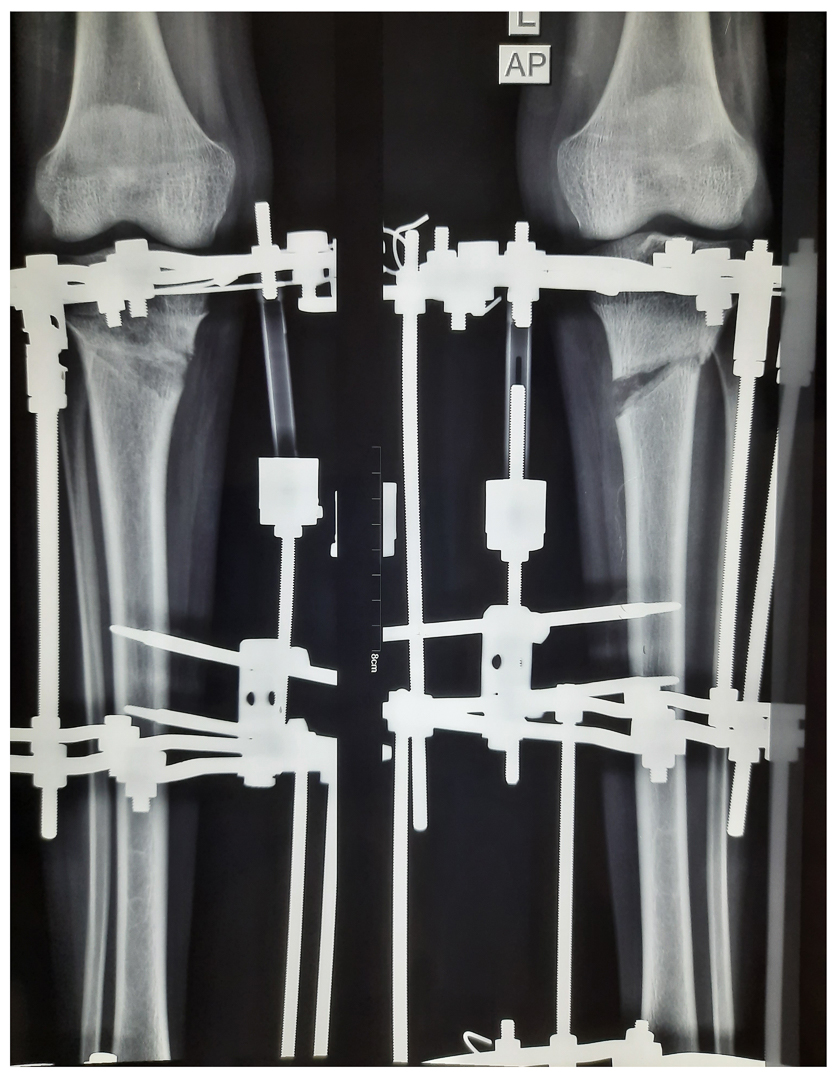

Genu Varus corrected by Osteotomy and gradual correction with Ilizarov

Osteotomies is required in patient where growth of bone stopped further or very sever deformity where growth modulation will unlikely to correct that much deformity. Osteotomy can fixed by plate or external fixater system

Gradual correction by corticotomy and bone transport by LRS System/ ilizarov.